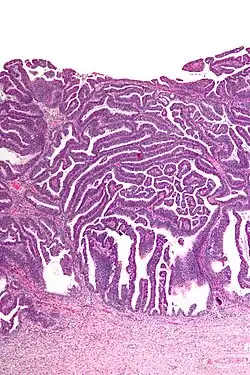

| Micrograph of a villoglandular adenocarcinoma the cervix. H&E stain. | |

The name of the lesion describes it microscopic appearance. It has nipple-like structures with fibrovascular cores (papillae) that are long in relation to their width (villus-like), which are covered with a glandular pseudostratified columnar epithelium.

Very low magnification -